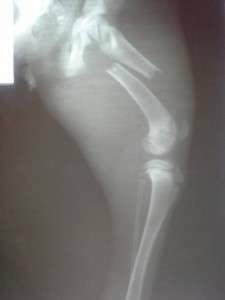

He was living his life in a market, where people threw him a bit of bread at times. At night, he took shelter under the market stands, or under a car parked in the market place. Yet, everything turned into a nightmare, when a car backed up and the poor dog couldn’t get out of the way. He was left there unable to move, while the heartless person who hit him abandoned him and went on with his life. A desperate call from a lady who worked at the market drew our attention, and we could not ignore the situation, although we are swamped with animals and problems of all kinds. The little dog’s first surgery was successful, and now he is at the clinic, where he will have to undergo more surgery. We hope that in the end he will walk again.

Hit by a car